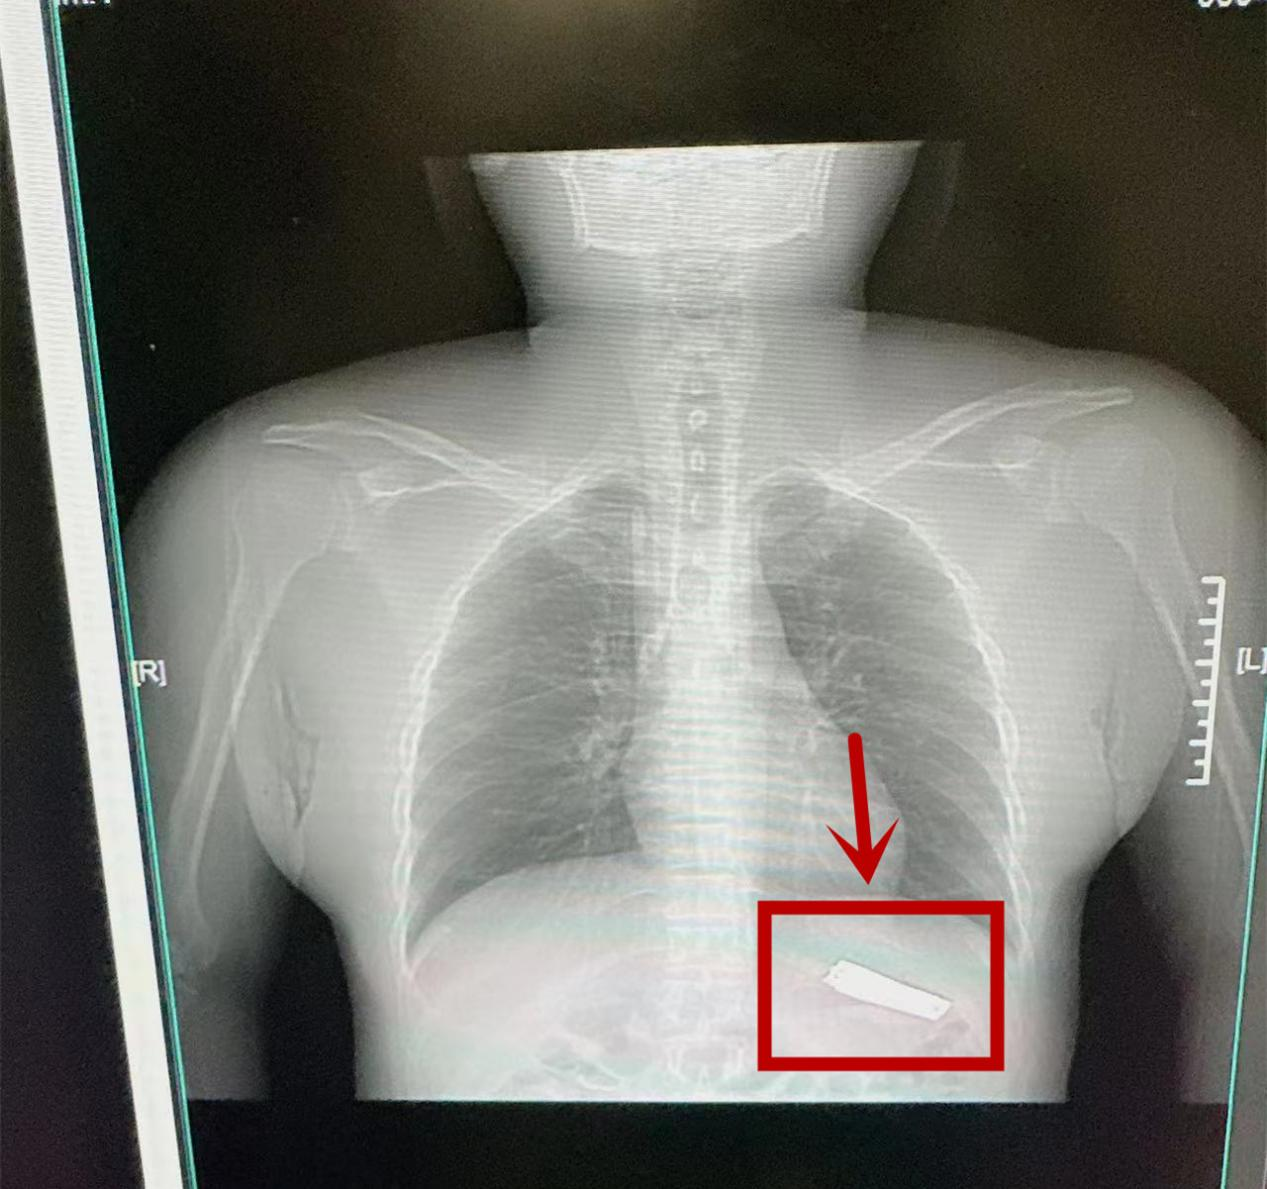

9月9日下午2点,安化县第二人民医院接诊一名吞指甲钳精神疾病患者,因患者吞服异物体积较大,医院立即开启绿色通道,组织消化内科、麻醉科、影像中心进行多科会诊

检查发现,指甲钳已进入患者胃内,若不及时取出,指甲钳会继续向下蠕动划伤消化道粘膜,将引起梗阻、出血、穿孔等情况。消化内科专家团队通过详细检查,反复对比异物钳圈套器与指甲钳实物大小,在无痛麻醉下利用圈套器在胃镜下成功将指甲钳取出。术后,患者生命体征平稳